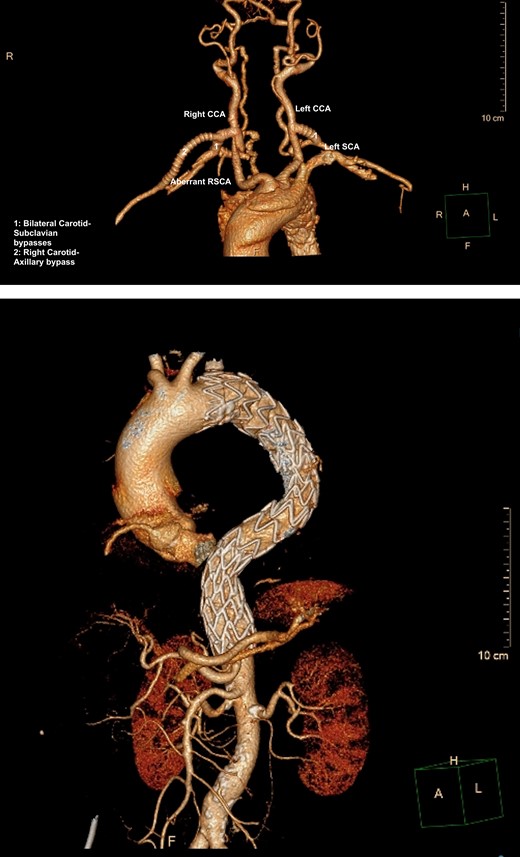

A semi-urgent endovascular thoracic aorta repair (TEVAR, Navion, Medtronic) was performed, with bilateral carotid–subclavian (C-S) bypasses. Intraoperatively, the IMH was noted have progressed to involve the usual mid-segment of the subclavian artery. As a result, a further bypass onto axillary artery was required. She made an uneventful recovery with follow-up imaging at 7 days and 1 month postoperatively showing slow resolution of her IMH and patent bypass grafts (Fig. 2A, B).

(A) 3D-CT reconstruction of extra-anatomical debranching of supra-aortic vessels with bilateral C-S bypasses. (B) 3D-CT reconstruction of thoracic endovascular repair.